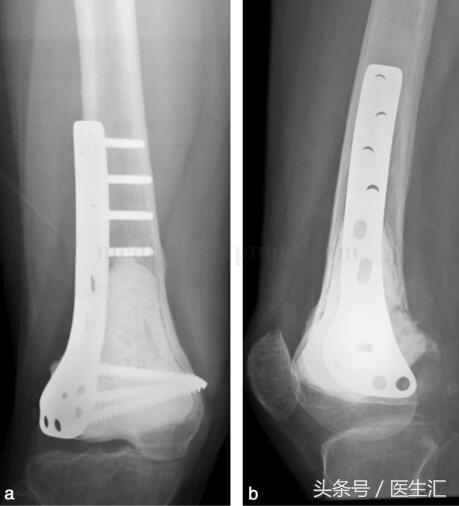

由于行軟骨下骨處植骨,故囑患者術(shù)后3個(gè)月,攝片示植骨愈合后,患肢開始負(fù)重(圖29‐4a,圖29‐4b)。此患者已術(shù)后隨訪兩年,局部無復(fù)發(fā),胸部無轉(zhuǎn)移,植骨已愈合,功能良好。

圖29‐4

a﹒術(shù)后X 線正位片;b﹒術(shù)后X 線側(cè)位片